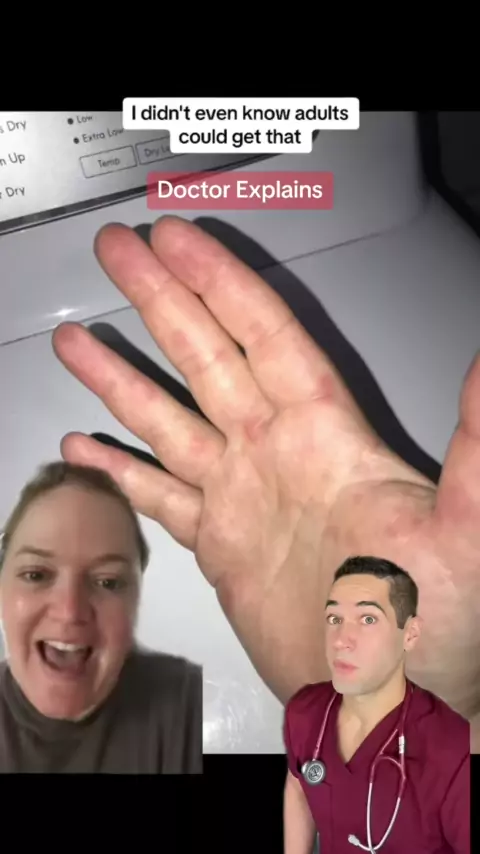

Dana • FootDocDana Se esta é a mão, como seria um pé? # microscópio # médicos # mão # bruto # sujo # germes